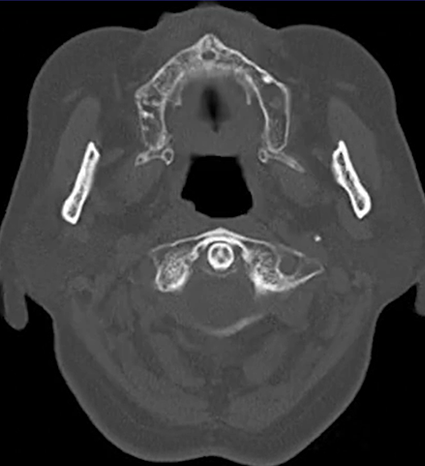

70歳男性。 6か月前から固体や液体を飲み込むのが徐々に困難になり、誤嚥が頻繁に起こるため内科受診となった。 身体所見では、肺野にcoarse crackleを…